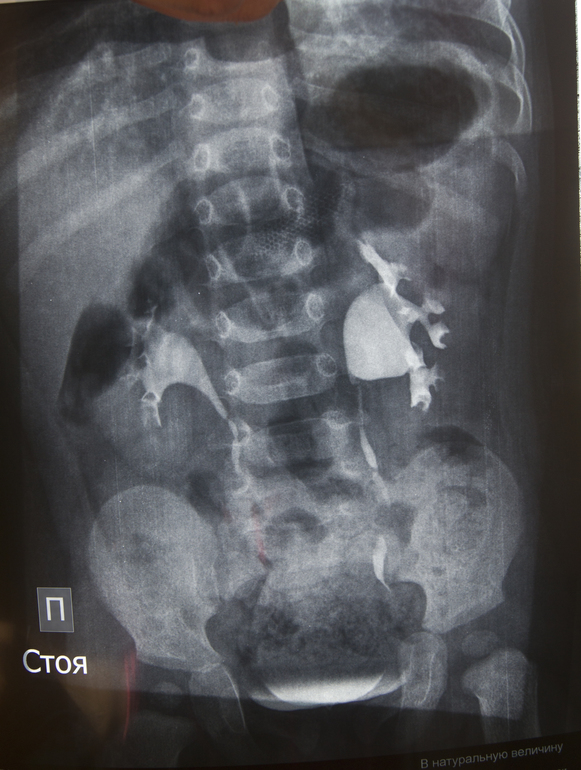

Ситуация 1: ребенку 1 год и 3 мес, в год прошли обследование (в/в уро- и цистография с контрастом), был поставлен диагноз "левосторонний гидронефроз 1 ст, фимоз". На апрель назначена операция по удалению крайней плоти. Нефролог говорит, что пока основной причиной гидронефроза признается именно фимоз. Дополнительных исследований (например, доплерография сосудов почек) не назначалось. Мой вопрос заключается в том, как часто (если таковое вообще возможно) фимоз может стать исключительной причиной гидронефроза? Если дело только в нем, операция окажется оправданной, если же препятствие в другом месте, ребенку предстоят "лишние" испытания, ведь вероятность того, что физиологический фимоз пройдет сам, высока. Для полноты картины я могу предоставить оцифровку рентгеновских снимков и выписку из истории болезни.

Если возможно, не могли бы Вы оценить результаты рентгенографического обследования моего младшего сына? На сколько качественно, на Ваш взгляд, были сделаны снимки? Согласно заключению нефролога, рефлюкс исключен. Если есть стриктура мочеточника (любой этиологии), должна ли она визуализироваться на рентгеновском снимке, или бывают случаи, которые проще диагностировать на УЗИ с диуретиком?

Я не берусь судить заочно, думаю слева нужно посмотреть на предмет абберантного сосуда в проекции пиело-уретрального сегмента